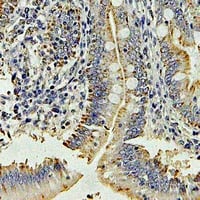

IHC (Immunohiostchemistry)

(Immunohistochemical analysis of DPP3 staining in human colon cancer formalin fixed paraffin embedded tissue section. The section was pre-treated using heat mediated antigen retrieval with sodium citrate buffer (pH 6.0). The section was then incubated with the antibody at room temperature and detected using an HRP conjugated compact polymer system. DAB was used as the chromogen. The section was then counterstained with haematoxylin and mounted with DPX.)